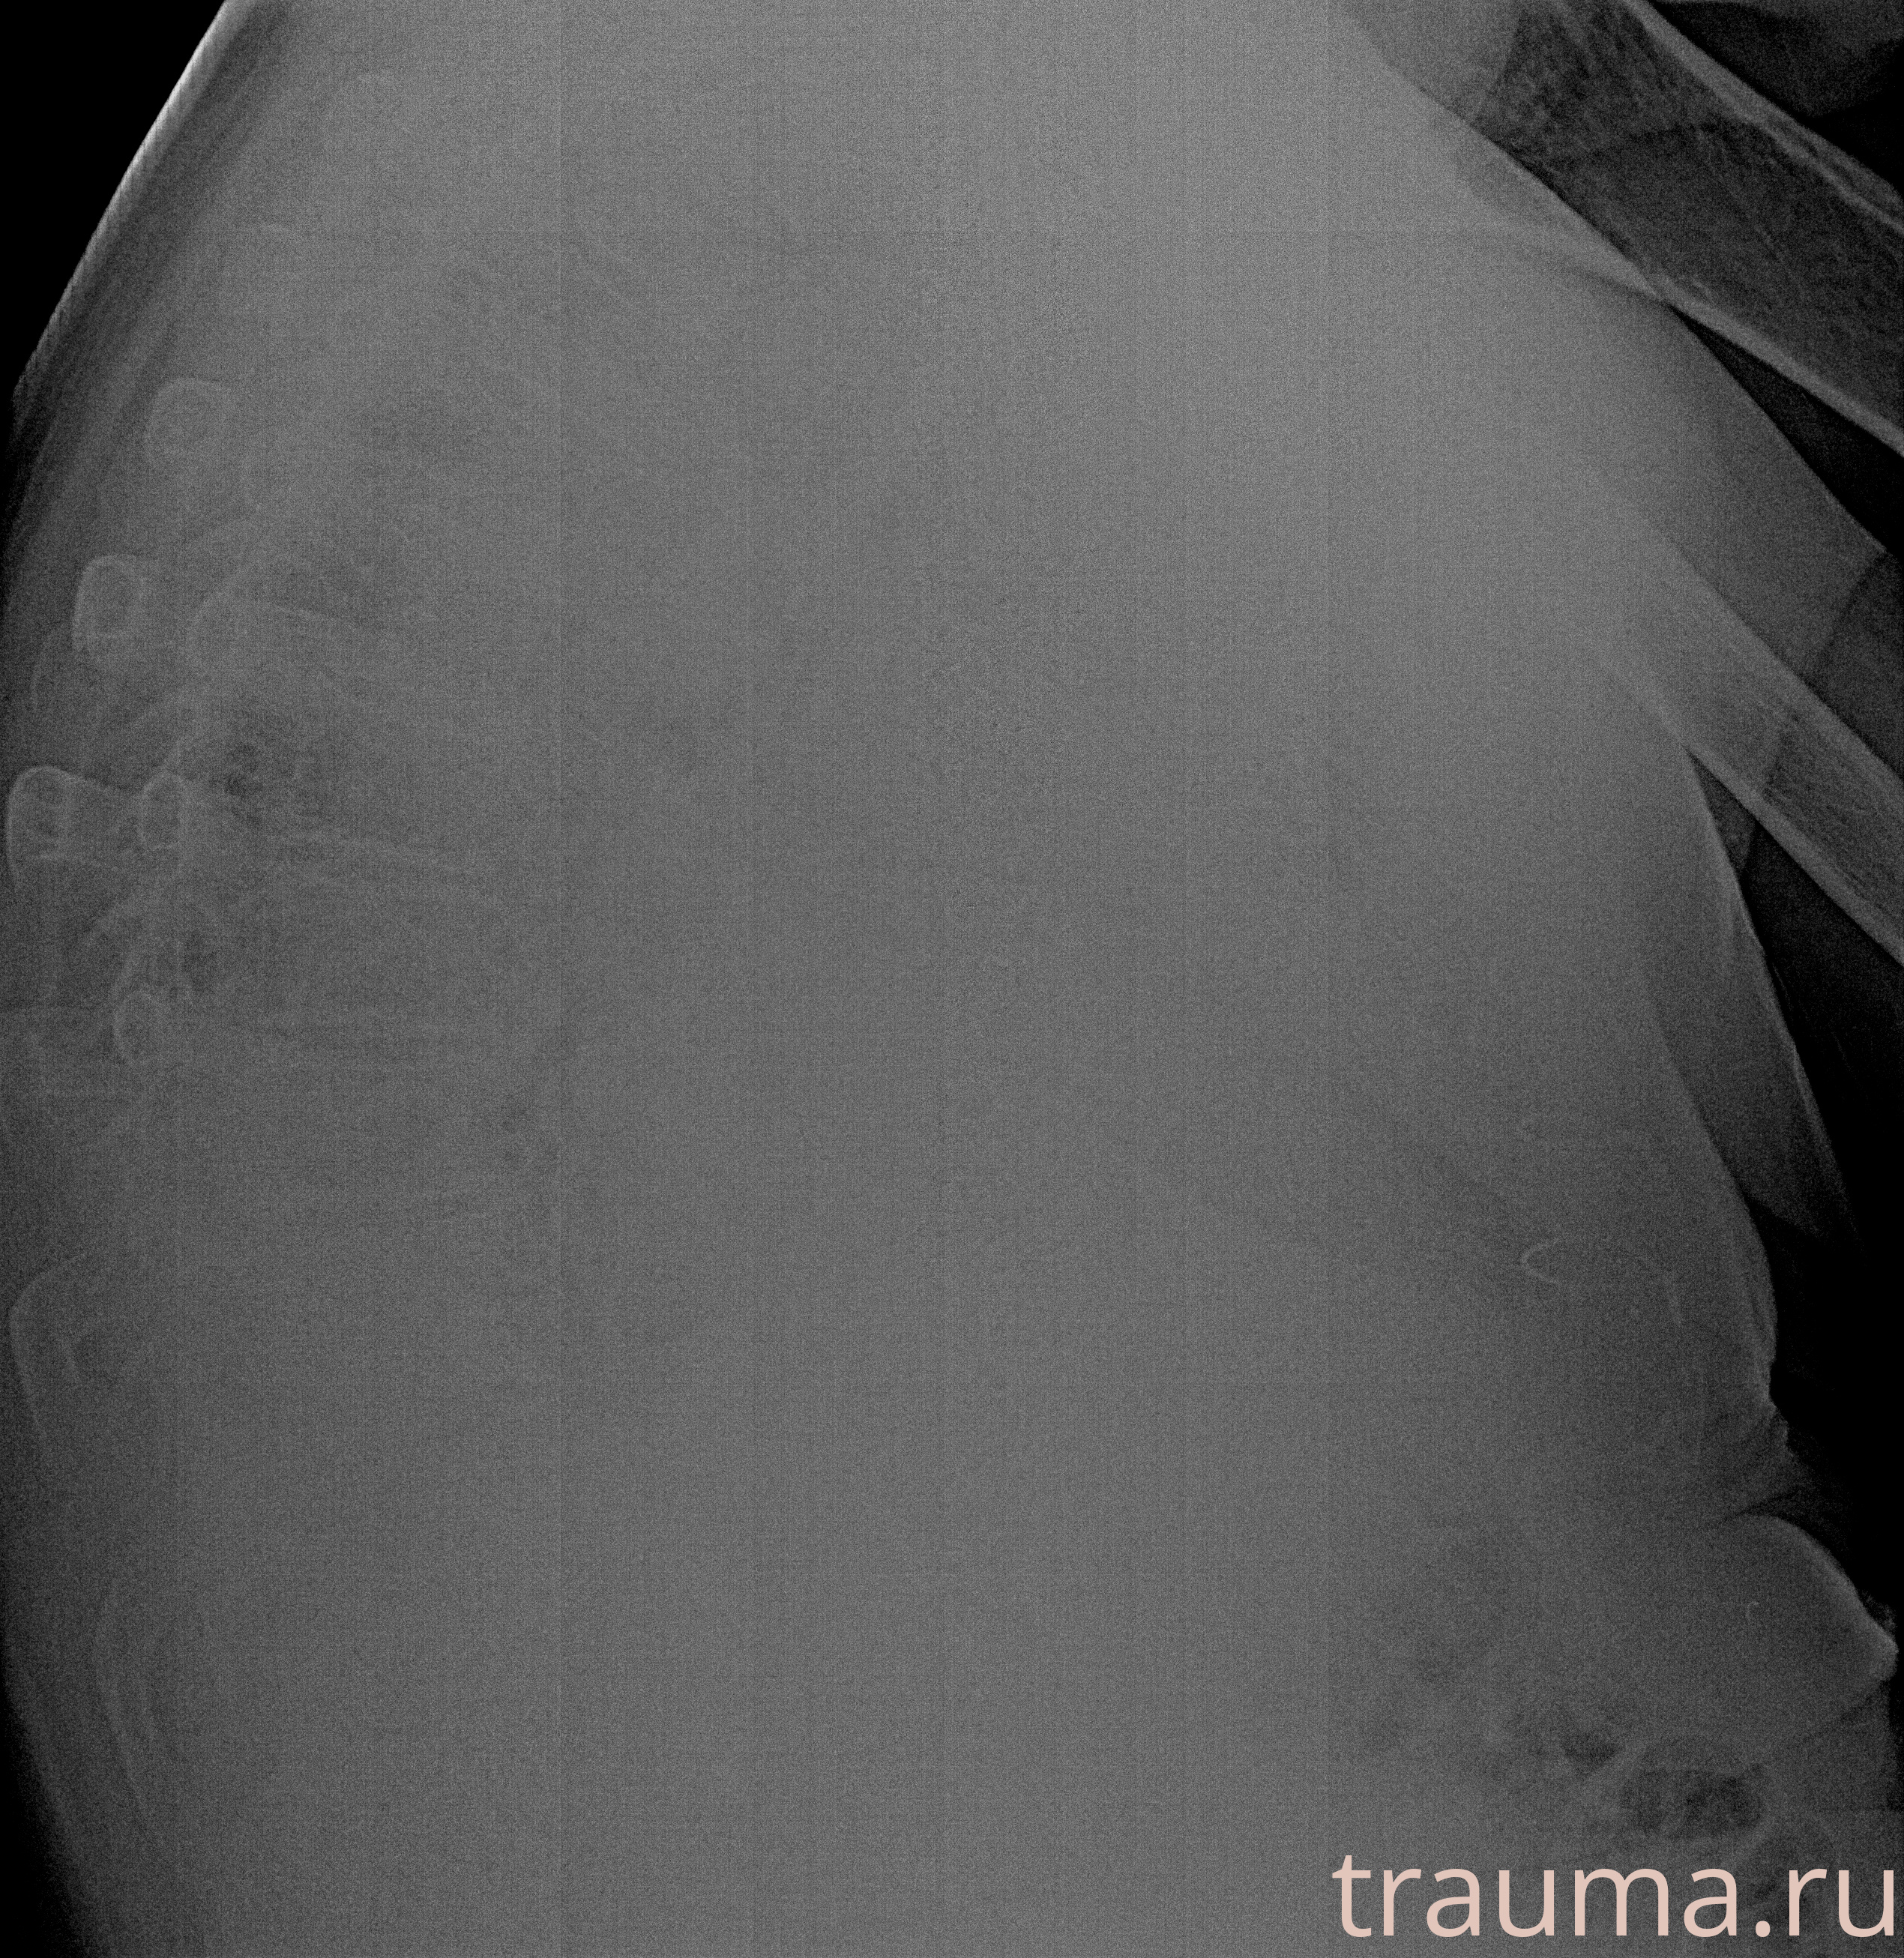

Рентген на дому: по вашему адресу приезжает врач-рентгенолог, травматолог-ортопед с мобильным рентгеновским аппаратом, проводит диагностику травмы или заболевания, делает необходимые рентгенограммы, дает рекомендации по дальнейшему лечению. Получить качественные снимки в домашних условиях возможно благодаря уникальной методике, разработанной МосРентген Центром для института  Склифосовского